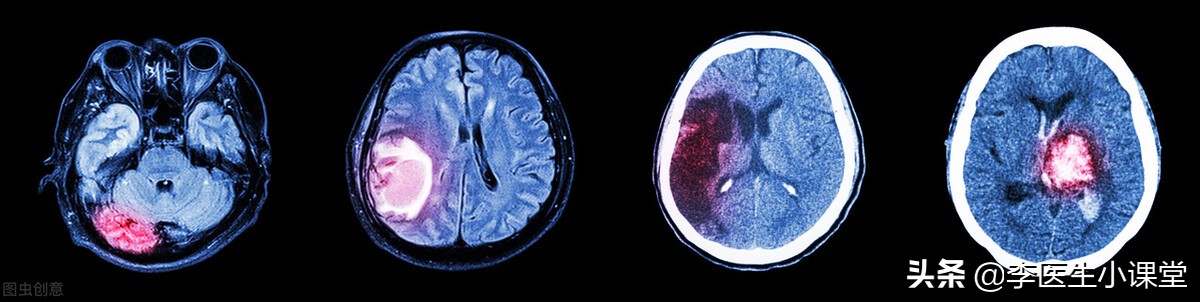

脑溢血也就是我们通常所说的脑出血(ICH), 是一种非外伤引起的脑实质内出血,血液从血管中溢出到脑组织中, 出血部位常出现在大脑半球、脑干以及小脑等处,在急性心脑血管疾病中脑出血患者占比较多,且致死率较高。

临床上根据大脑内血肿的发展过程,将其分为急性期、吸收期以及囊变期。

在临床上既可以根据患者不同的出血部位划分为脑干出血以及丘脑出血等多个类型,也可以根据不同的致病因素划分为原发性或者是继发性的脑出血,原发性脑出血是由非创伤性引起的,也属于自发性脑出血。